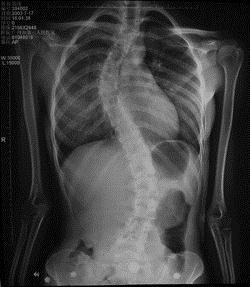

病历摘要: 患者××,女,17岁,发现剃刀背畸形3个月。查体:脊柱胸段向右侧凸,腰段向左侧凸,右胸廓呈剃刀背畸形,双下肢未见明显异常。脊柱侧弯的手...

问题 病历摘要: 患者××,女,17岁,发现剃刀背畸形3个月。查体:脊柱胸段向右侧凸,腰段向左侧凸,右胸廓呈剃刀背畸形,双下肢未见明显异常。 脊柱侧弯的手术并发症?

选项 A、感染 B、断钉断棒 C、假关节形成 D、融合失败 E、脱钩脱钉矫正失败 F、曲轴现象 G、脊髓损伤引起的截瘫

答案 ABCDEFG

解析 ABCDEFG